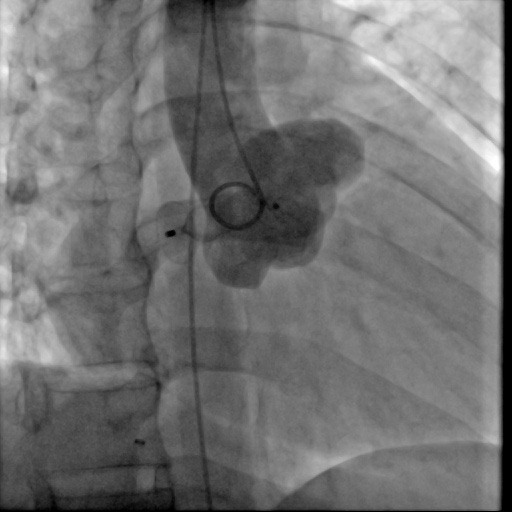

图:患者术前